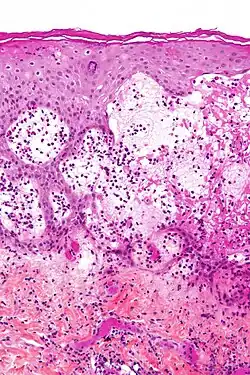

Micrograph of gestational pemphigoid showing the characteristic subepidermal blisters and abundant eosinophils. HPS stain. | |